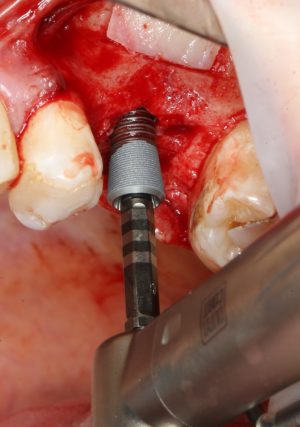

Следующей мы используем фрезу 2.0/3.2:

Такие фрезы — особенность имплантационной системы Astra Tech. Они нужны для того, чтобы не разломать края лунки и сделать переход между фрезами (а мы переходим с 2.0 на 3.2 мм) более точным и плавным, благодаря направляющей 2.0 мм. Однако, пройти лунку такой фрезой на всю глубину удаётся далеко не всегда. В таких случаях используется обычная спиральная фреза диаметром 3.2 мм (с зеленой полоской). Но в нашем случае такой необходимости нет, ибо выше только субантральное пространство, поэтому мы работаем только вот такой двойной фрезой.

После этого можно еще раз (последний, кстати), проверить направление и ангуляцию оси будущего имплантата. Всё тем же вышеозначенным пином:

Если бы мы хотели поставить имплантат диаметром 4.5 мм, то далее мы перешли бы к кортикальной конической фрезе. Однако ж, я посчитал, имплантат диаметром 5.0 мм в данной клинической ситуации будет более надежным и органичным, поэтому мы продолжаем подготовку лунки. И следующая используемая фреза — 3.2/3.7 — то же самое. что и предыдущая, с направляющей 3.2 мм: